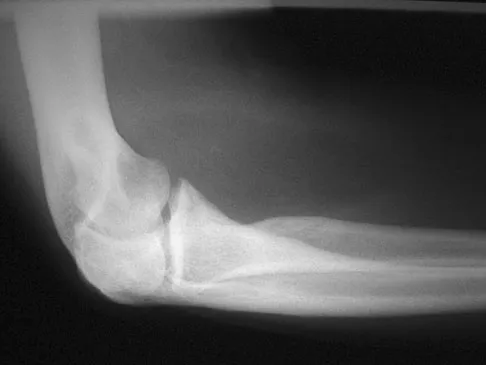

Figure 12 shows a lateral radiograph of the elbow. What is the most likely diagnosis?